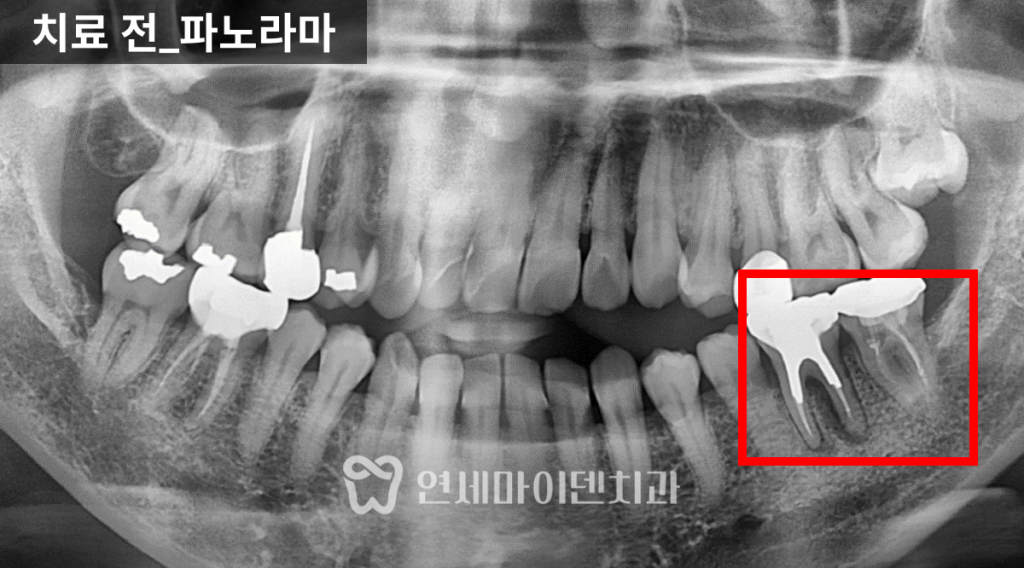

이번 케이스는

잇몸이 자주 붓고 출혈이 있으며,

고름이 반복되는 상태였습니다.

아래 어금니 한 부위

이미 크게 파절되어 있었고,

주변 잇몸에는

치석과 염증이 많이 축적되어 있었습니다.

이런 경우 해당 치아는

기능적으로 유지가 어렵고

염증의 중심이 되는 경우가 많습니다.

인접한 치아들을 확인해보니

약간의 흔들림은 있었지만,

치주 치료와 관리가 병행된다면

충분히 유지 가능한 상태였습니다.

치료 전 방사선 사진을 보면

치아가 쓰러진 문제도 있었지만

무엇보다 뼈의 폭과 높이가

많이 줄어든 상태

였습니다.

잇몸도 전반적으로 약했고,